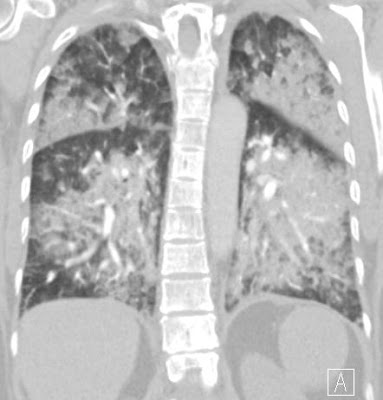

ground-glass opacities mixed with consolidation; typically the GGO forms the edge of the opacities

spared costophrenic angles

prominent septal lines only in the area of the GGO indicating, the subacut phase, when resolution begins; opacities are mainly gravity dependent

partial resolution in a few days